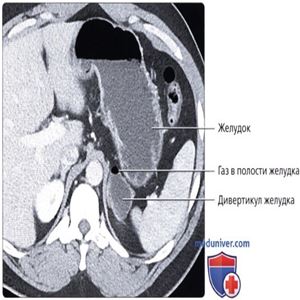

КТ с контрастированием, аксиальный срез: определяется кистозное «объемное образование», растущее вблизи левого надпочечника. Хотя это образование при поверхностной оценке может быть ошибочно принято за гиподенсное объемное образование или кисту надпочечника, обратите внимание на наличие мелкого скопления газа, расположенного внутри, что говорит о наличии сообщения с ЖКТ. Это классическая локализация и внешний вид дивертикула желудка и при тщательной оценке обычно может быть обнаружено сообщение с желудком.